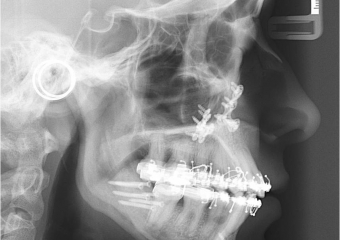

Telerradiografia após a cirurgia